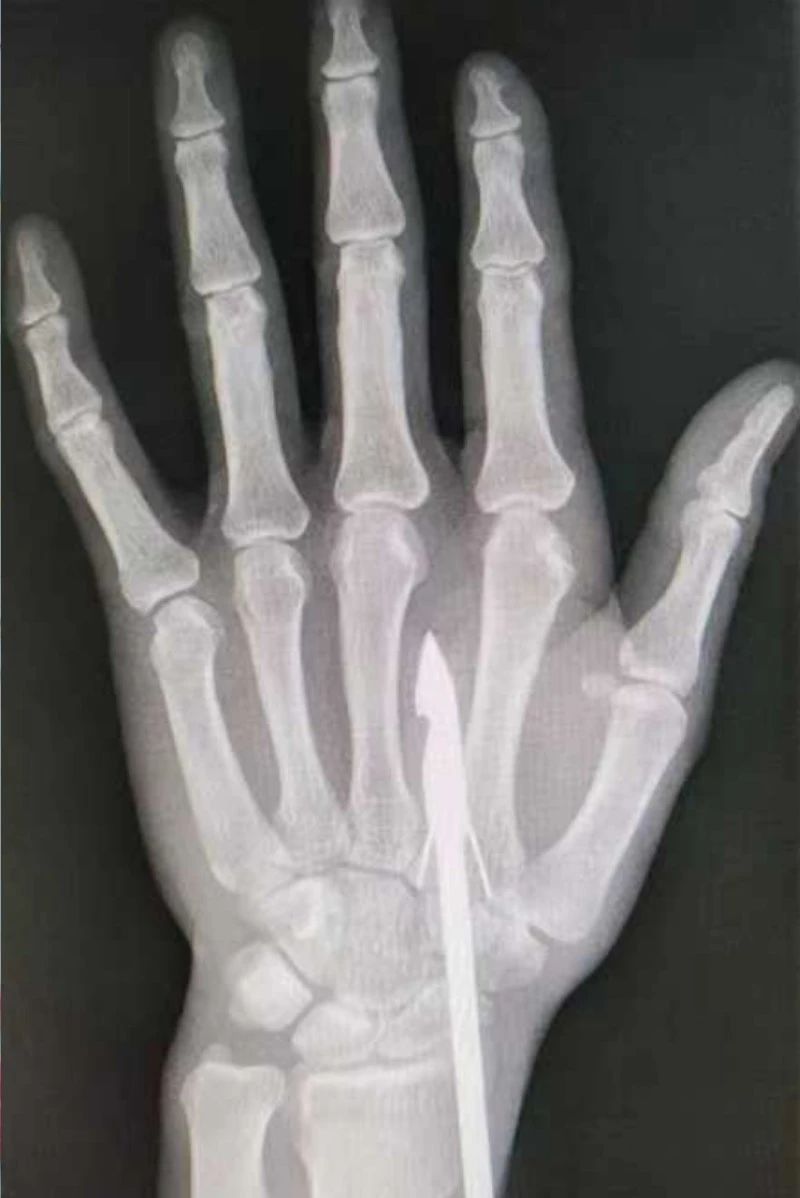

時(shí)間緊迫,每一秒的流逝都可能對傷者的手部功能造成不可逆的損害。接診醫(yī)生代彭威,迅速對傷者進(jìn)行了初步檢查。他注意到,魚鉤已經(jīng)深深嵌入皮膚,情況遠(yuǎn)比表面看起來復(fù)雜。沒有絲毫猶豫,立即安排了X線檢查以確認(rèn)魚鉤的位置及傷及范圍,以及急診化驗(yàn)檢查以評估患者的整體狀況。

確保在取出魚鉤的同時(shí),不對周圍的組織造成額外的傷害。8點(diǎn)15分左右患者在局部浸潤麻下進(jìn)行手術(shù),經(jīng)探查后魚鉤未傷及重要血管、神經(jīng)及肌腱,經(jīng)過緊張的十分鐘,魚鉤終于被順利取出,隨后對傷口進(jìn)行了仔細(xì)的清理和縫合,用敷料仔細(xì)包扎,確保傷口能夠順利愈合。